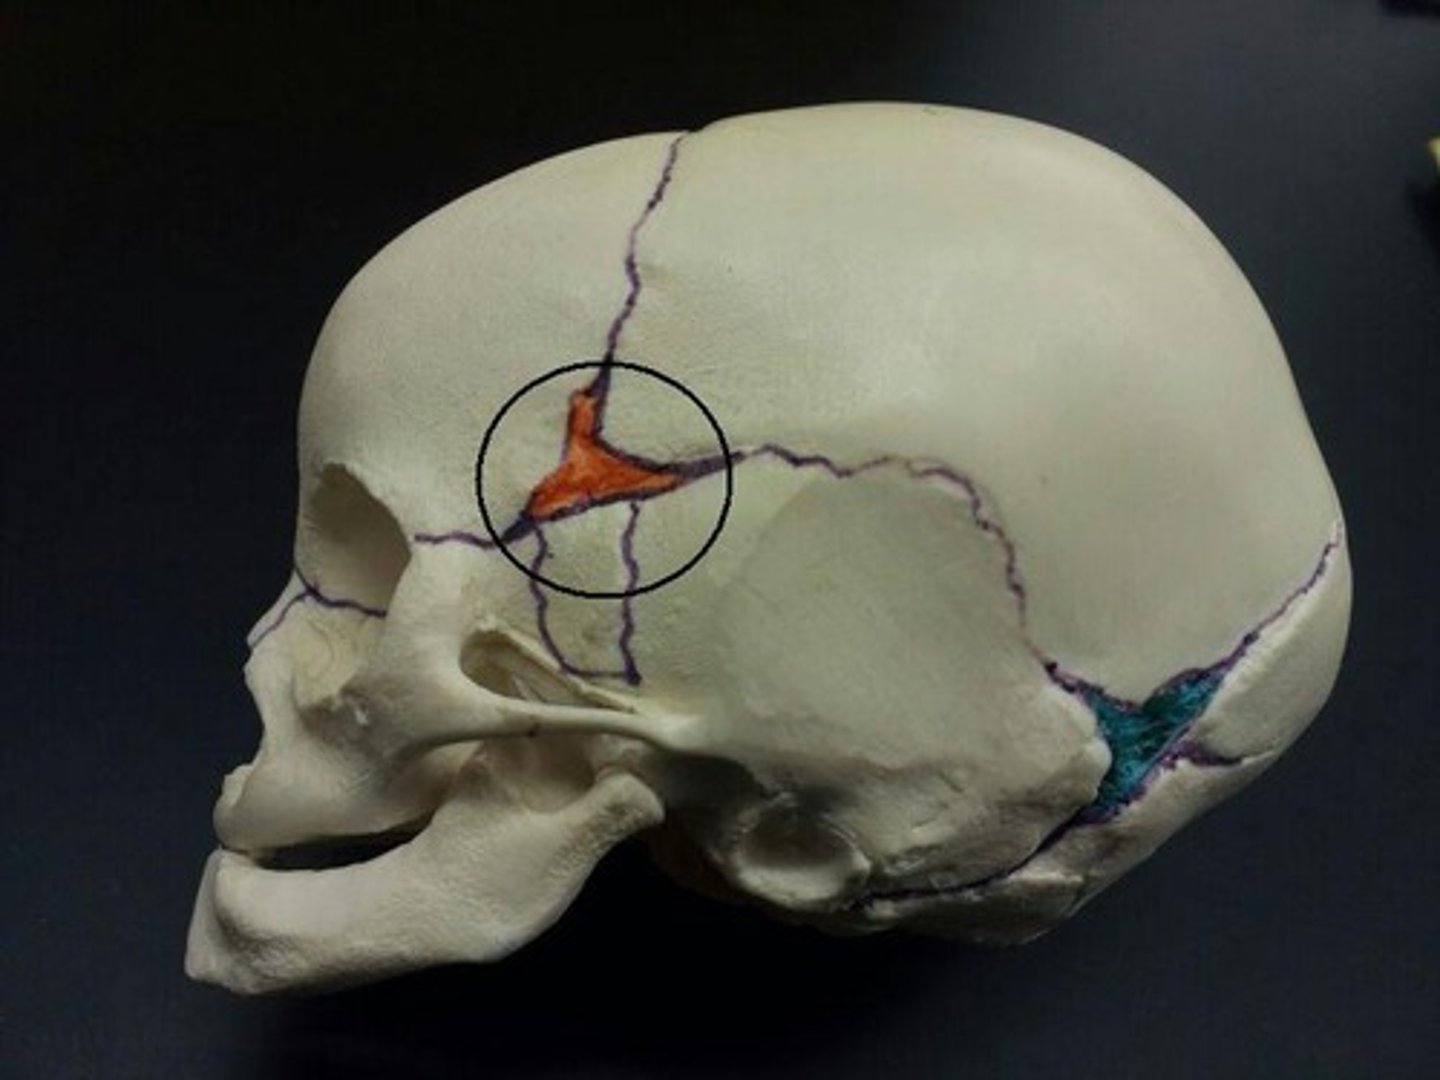

pterion

asterion